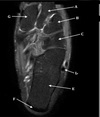

How well did you know this?

1

Not at all

2